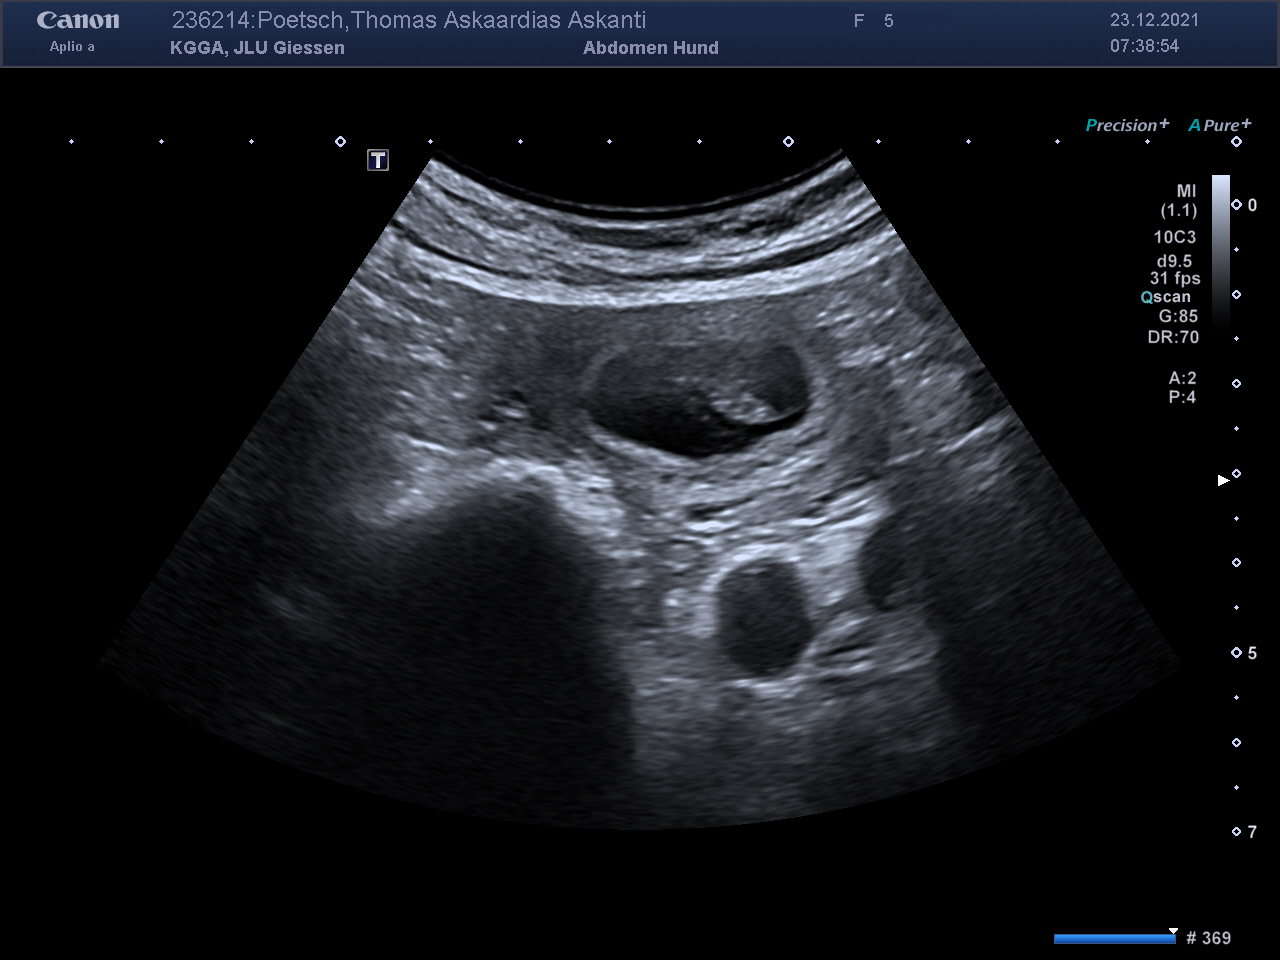

Es passiert jeden Tag, jede Stunde und wahrscheinlich auch jede Sekunde, dass neues Leben auf die Welt kommt. Es ist so alltäglich und für uns doch wieder etwas ganz Besonderes. Vielleicht, weil es bei uns zuhause im Wohnzimmer passiert oder weil es unsere Askanti ist oder weil wir dabei sein dürfen oder, oder, oder ……

Details